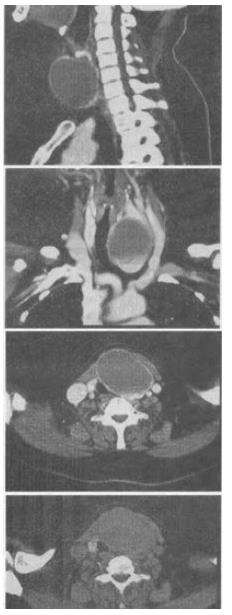

3、 女,56岁,发现颈部肿块1个月余,CT如图所示,最可能的诊断是()。

- A、甲状舌管囊肿

- B、甲状腺乳头状癌

- C、甲状腺原发淋巴瘤

- D、甲状腺腺瘤

- E、甲状腺脓肿